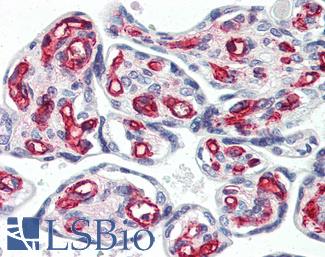

KRAS

Anti-KRAS antibody IHC of human placenta. Immunohistochemistry of formalin-fixed, paraffin-embedded tissue after heat-induced antigen retrieval. Antibody LS-B4683 concentration 5 ug/ml. This image was taken for the unconjugated form of this product. Other forms have not been tested.